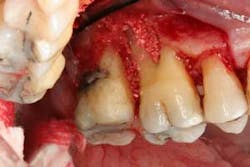

Figures 7a, 7b, and 7c: Osseous surgery in the mandibular anterior sextant with debridement of root surfaces and then regeneration.

Briefly, during osseous surgery, the upper right molars were treated with a combination of autograft and platelet-derived growth factor/Beta-tricalcium phosphate along with a porcine collagen graft (figures 5a and 5b). The upper left osseous surgery consisted of the same treatment (figures 6a and 6b), but also included the extraction of a hopeless tooth No. 15. Once again, the anterior osseous surgery consisted of the same regenerative materials as the former surgeries but with the addition of a porcine soft-tissue graft (figures 7a, 7b, and 7c). After the initial healing phase, the patient was placed on a strict home-care regimen and was seen every eight to 12 weeks for hygiene recare. The patient maintained excellent hygiene throughout the five-year follow-up period.